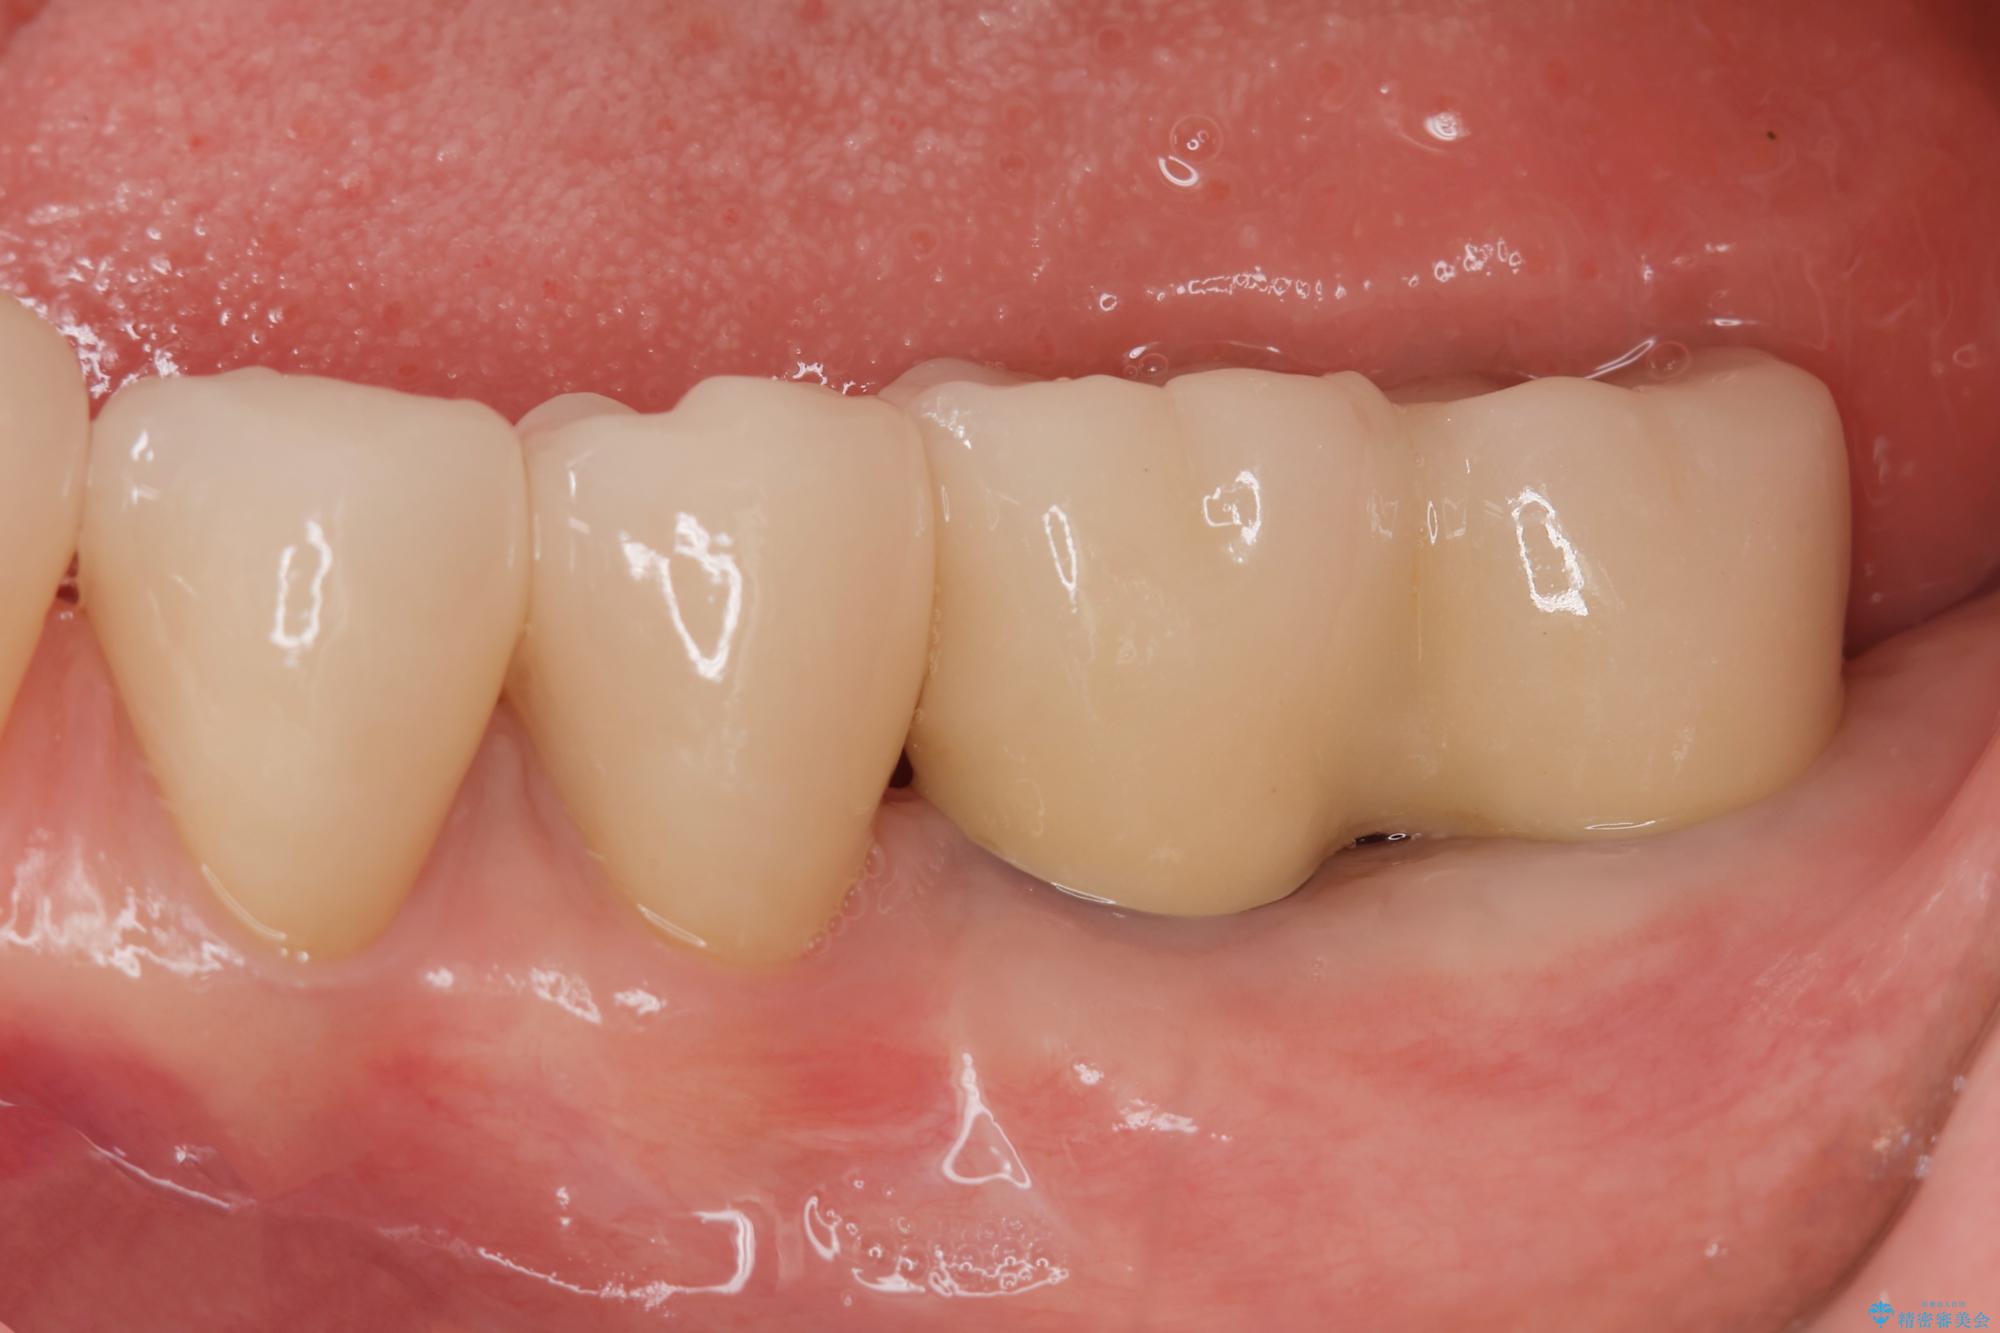

治療後

劣化の進んだブリッジの再治療[ 不適合な補綴物による虫歯の再発 ] 治療後画像 劣化の進んだブリッジの再治療[ 不適合な補綴物による虫歯の再発 ] 治療後画像 劣化の進んだブリッジの再治療[ 不適合な補綴物による虫歯の再発 ] 治療後画像